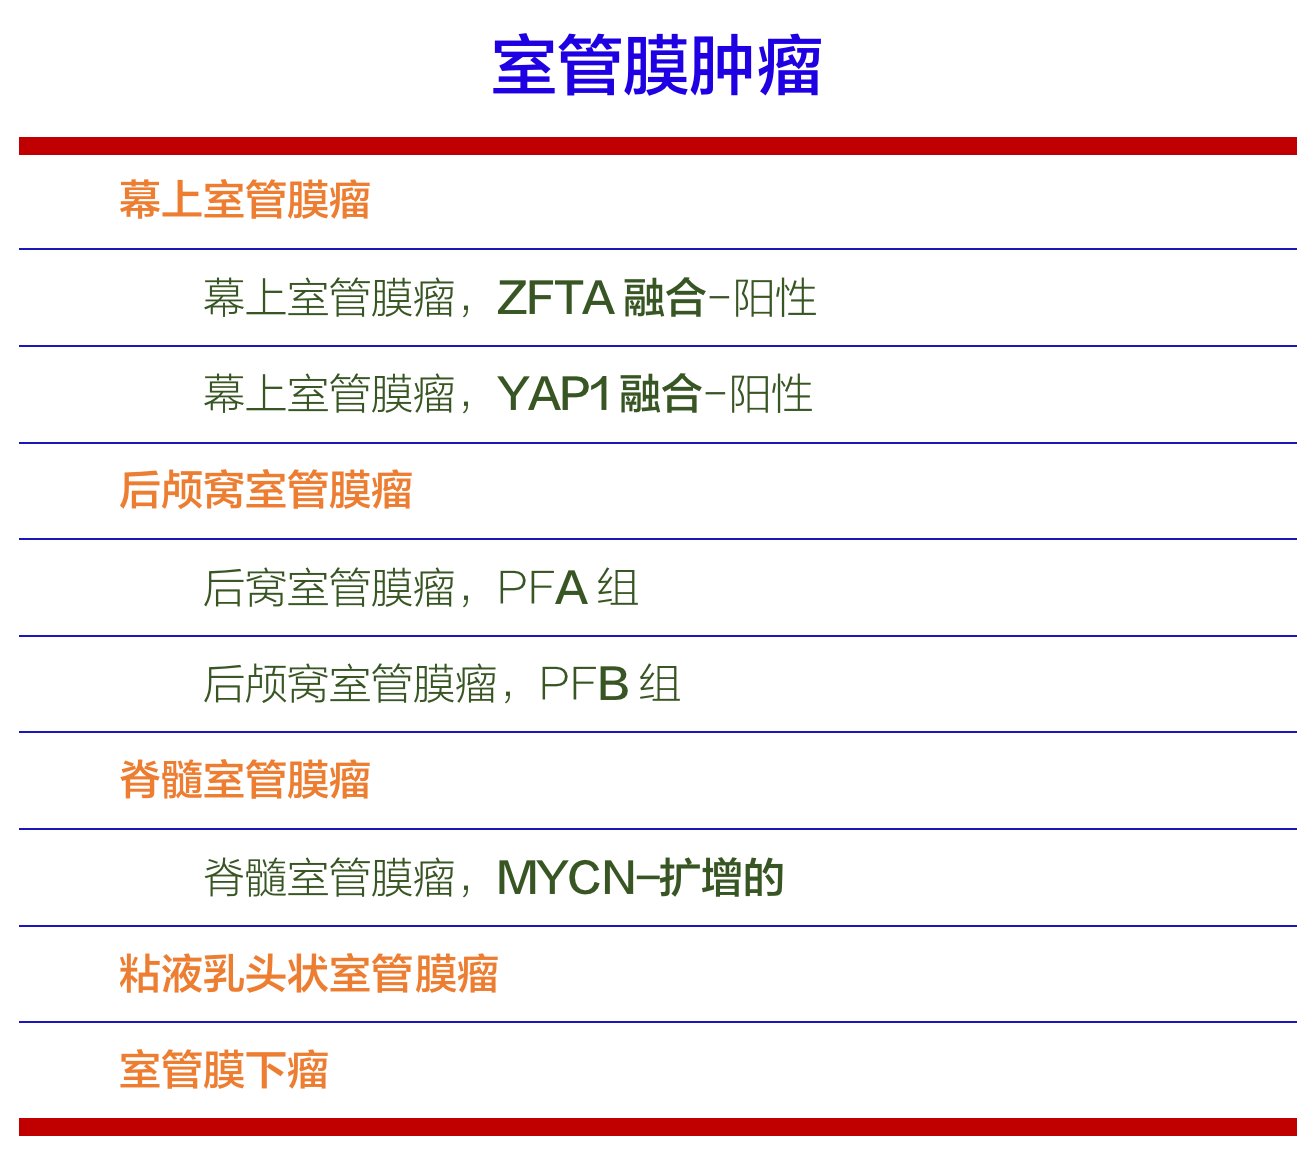

室管膜瘤的2021分类,将它们分成幕上、后颅窝、和椎管内三个组。

新分类特别列出了两种由分子特征定义的幕上室管膜瘤类型:

①具有ZFTA融合的,这是针对C11orf95的新名称,认为比RELA融合更能代表肿瘤类型,因为它的数量可能比RELA融合更多;

②具有YAP1融合的幕上室管膜瘤。

新分类还增添了2种由分子特征定义的后颅窝室管膜瘤类型,即A组和B组,以及一种因为存在MYCN扩增的脊髓内。